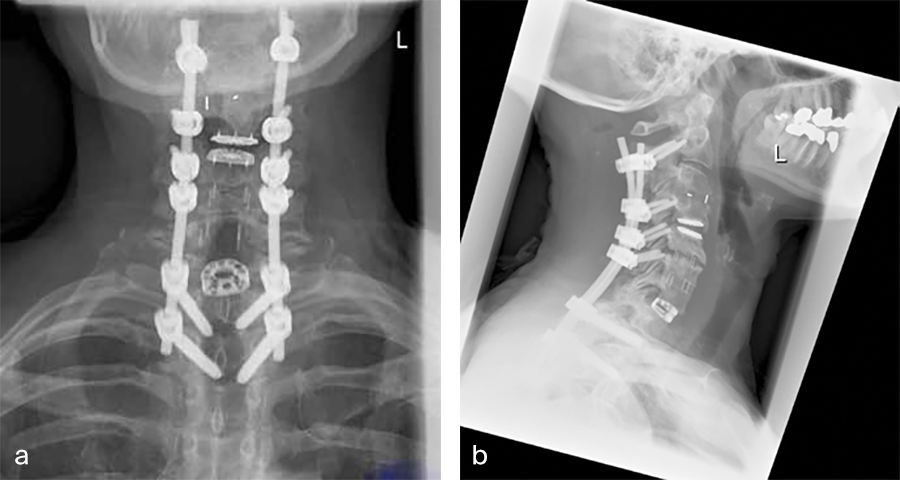

Second, a posterior revision surgery was performed including implant removal of the posterior instrumentation between C2 and C4 followed by a laminectomy of C7 with bilateral foraminotomy of the C8 nerve routes. Re-instrumentation with isthmic screws at the level C2, lateral mass screws at the level C4, C5, and C6, as well as bilateral pedicle screws at the level T2 and T3 was performed using the new Symphony system (DPS). The Symphony system offered the opportunity to place 4.0 mm screws in the previous loosened screw location at the level C2. The 3.5 mm screws were placed in C4, C5, and C6, and 5.5 and 5.0 mm screws at T2 and T3, respectively. The 4.0 mm rod allowed a good direct connection between the cervical spine isthmic and lateral mass screws and the thoracic pedicle screws, providing adequate stability and allowing excellent reduction. An intraoperative image is shown in Fig 5. Postoperative x-ray evaluations are displayed in Fig 6ae.

Postoperative imaging (Fig 6a-e), showing:

AC DF C7/Th1 (Syncage C) and posterior stabilization with Symphony of C2, C4, C5, C6, Th1, and Th2 using 3.5 (C4/5/6) 4.0 (C2), 5.0 (TH2) and 5.5 mm (Th1) screws and 4.0 rods.